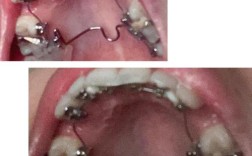

弯制过程可分为四个核心步骤,每个步骤均可通过图片清晰呈现,第一步是形成连接体:将弓丝弯制成“U”形,置于邻面龈沟内,图片需展示连接体与牙面贴合的紧密状态,避免过度压迫导致牙龈萎缩,第二步是弯制卡环臂:用钳子将弓丝沿牙面弧度弯制,形成类似“C”形的臂部,图片中需标注卡环臂的切入角(通常为20°-30°),角度过小会导致固位力不足,过大则可能刺伤黏膜,第三步是制作支托:在卡环末端弯制与牙面窝点状接触的支托,图片需强调支托的“匙形”形态,边缘圆钝以分散咬合力,第四步是整体调整:将弯制完成的卡环戴入模型,检查与牙面的密合度,图片可通过对比展示调整前后的差异,如卡环臂与牙面的均匀间隙、支托的稳定接触等。

不同牙齿位置的卡环弯制存在差异,可通过表格对比常见类型的特点与弯制要点,上颌第一磨牙常用改良箭头卡环,其弯制需注意箭头尖位于颊面中央窝,图片需展示箭头与牙尖的相对位置;前牙连续卡环则需弯制平滑的弧线,避免转折处锐利,图片可突出弧线的连续性与牙龈保护,弯制错误案例的图片对比尤为重要,如卡环臂角度过大导致的脱落、支托过高引发的咬合痛,这些直观图像能帮助医生快速识别并规避问题。

临床实践中,弯制图片还可作为教学工具,通过分步骤示意图(如原始弓丝→连接体形成→卡环臂弯制→支托添加→成品卡环)展示完整流程,配合文字说明关键动作要领,弯制卡环臂时需用三用钳夹住弓丝,以牙面为参照缓慢弯曲,避免用力过猛导致弓丝变形,图片中可标注钳子的握持位置与施力方向。